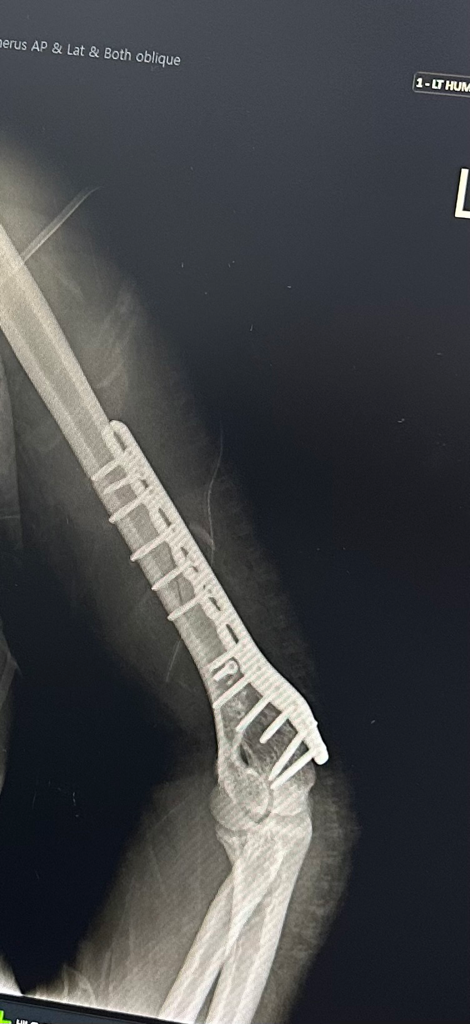

저번주 수요일 좌측 상완 분쇄고절 마비?

저번주 수요일에 분쇄골절되어 저번주 금요일 수술했습니다

점점 손가락이 움직여지긴 하는데 손목은 거의 안움직입니다

손가락과 손목의 폄이 잘 안될 가능성이 있어보이며 radial nerve의 기능이 떨어져있을 가능성이 있어보입니다.

1. 붓기때문에 근력저하가 생길수는 없고 일시적인지 영구적인지는 진찰을 해봐야겠지만 어찌됐든 신경마비가 생겼을 가능성이 높겠습니다.